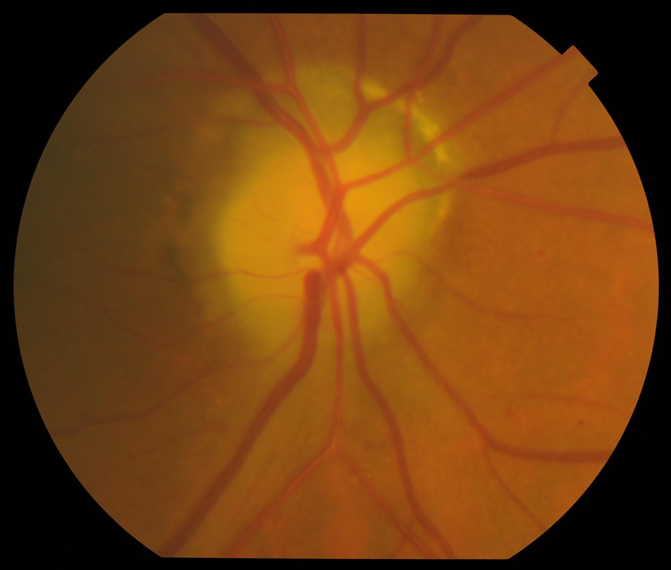

急性期非動脈炎性虚血性視神経症の視神経乳頭所見

視神経乳頭の辺縁が明瞭に見えず、神経線維が腫脹しており、乳頭浮腫を呈している。